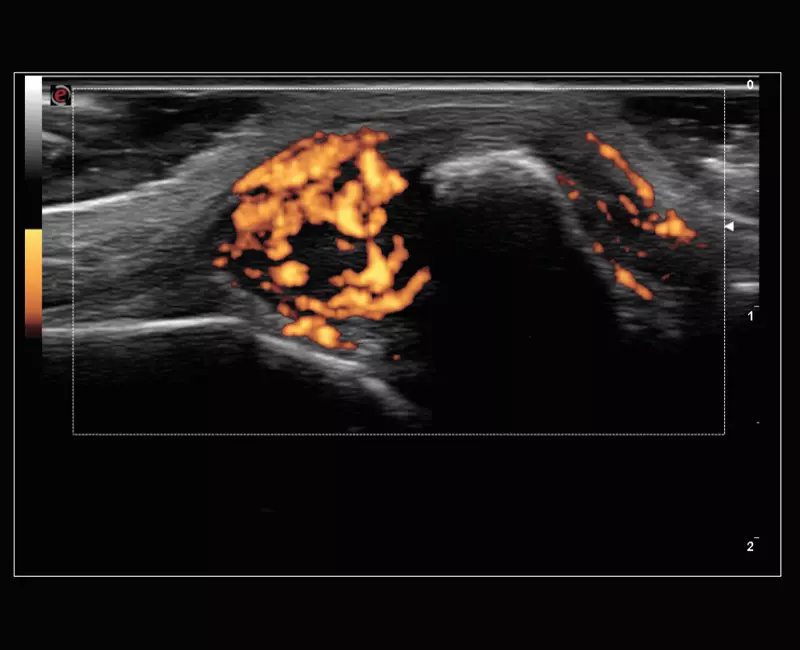

MyLab™9 Platform - XFlow in testis vascularization

MyLab™9 Platform - XFlow in testis vascularization

MyLab™9 Platform - High resolution imaging in testis

MyLab™9 Platform - High resolution imaging in testis